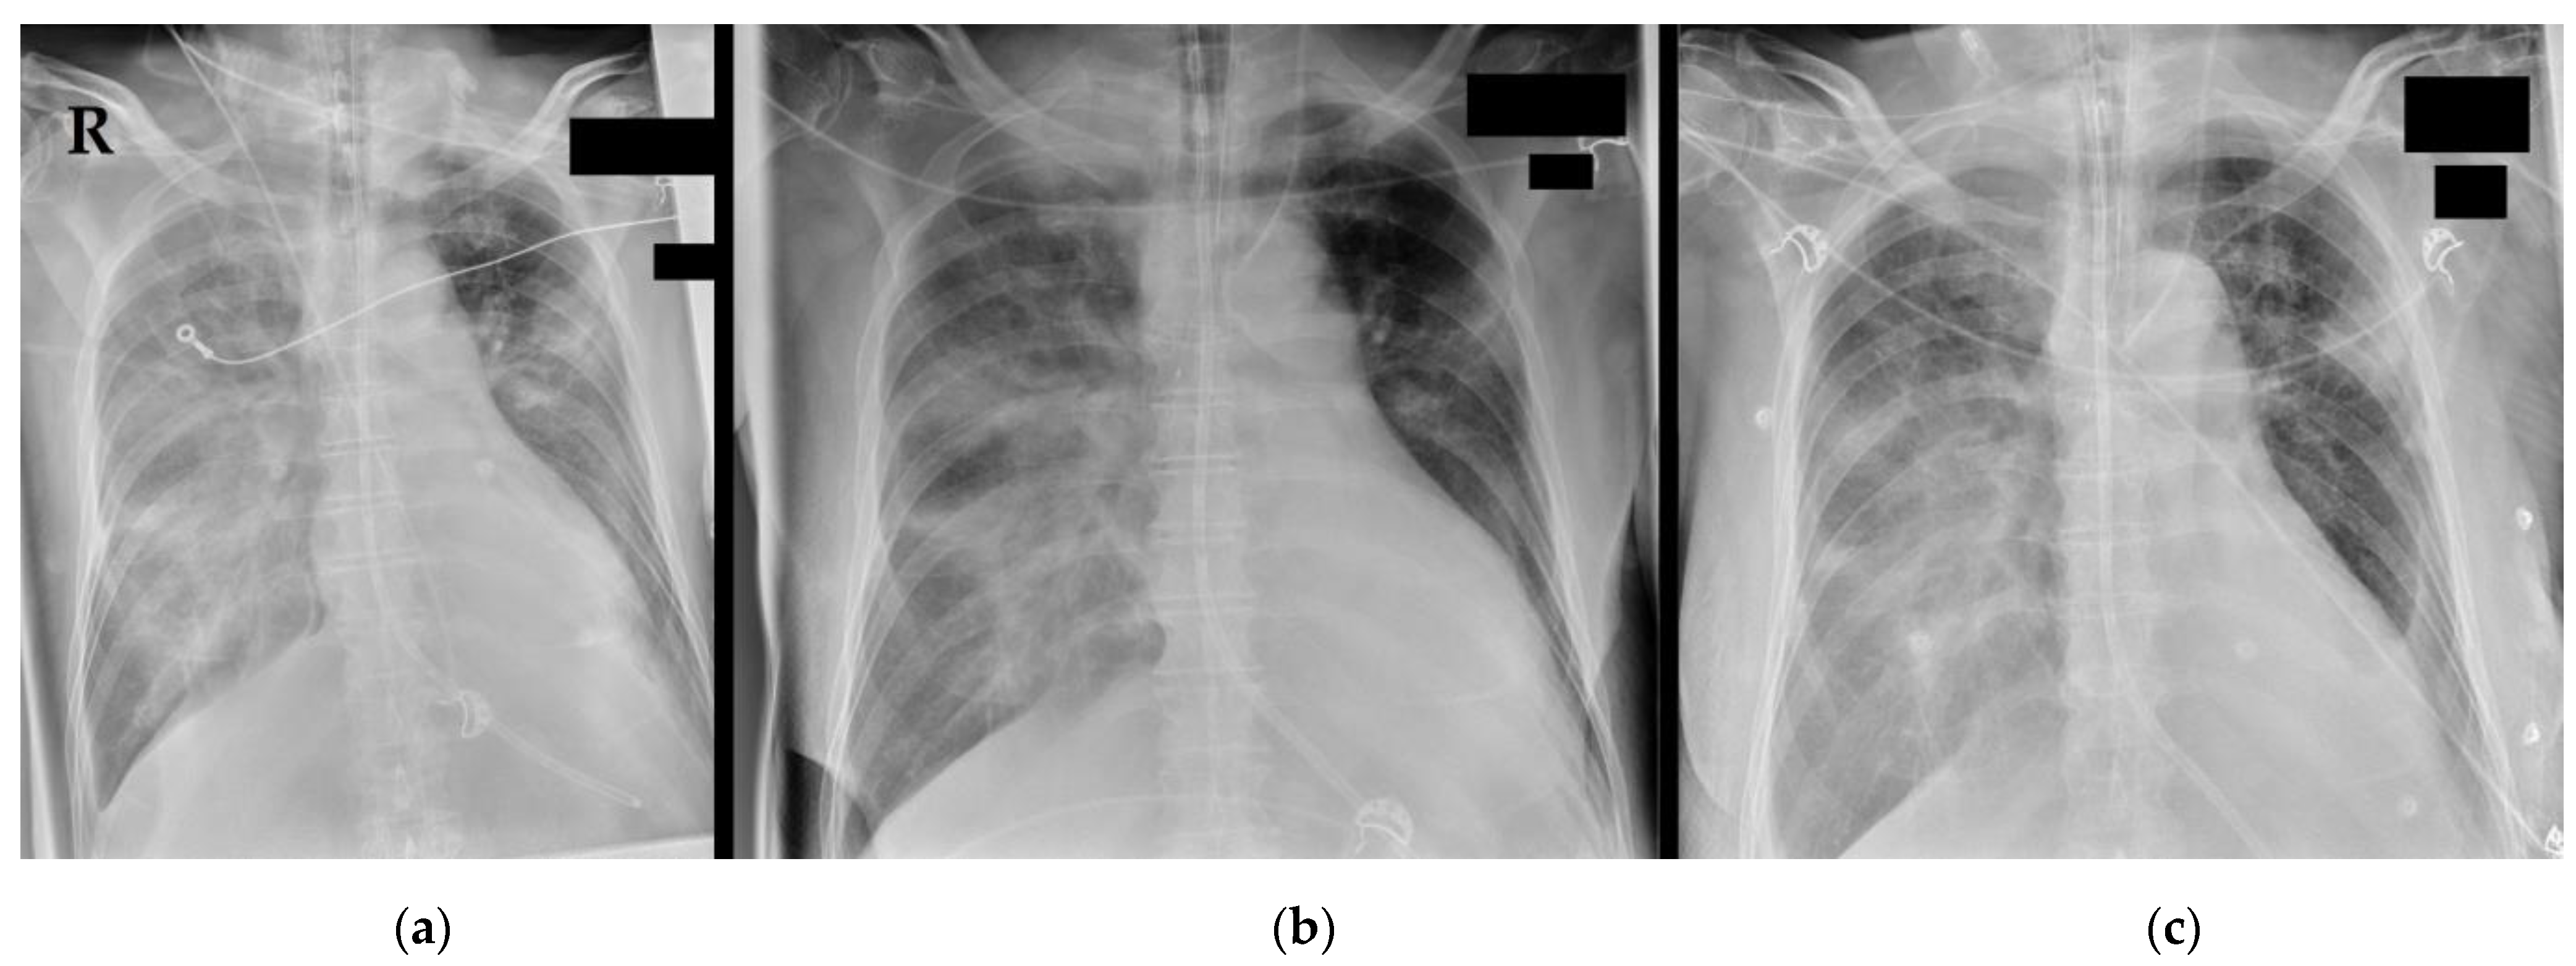

2. Surroundings and Materials

3.4. Further Diagnostics

3.5. Final Diagnosis and Deterioration